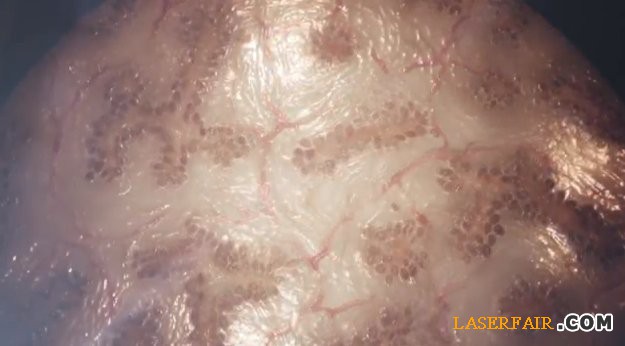

Organovo 3D

打印的肝臟組織樣品